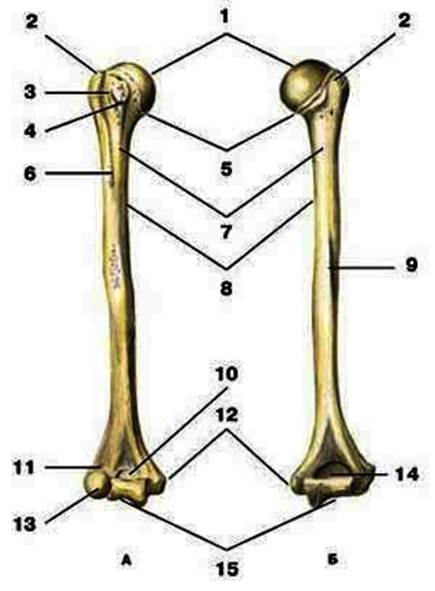

S: Цифра 1 обозначает головка плечевой кости.

S: Число 15 обозначает блок плечевой кости.

S: Цифра 5 указывает на хирургическая шейка плечевой кости.

S: Число 10 обозначает венечная ямка плечевой кости.

S: Число 14 указывает на локтевая ямка плечевой кости.

S: Цифра 9 указывает на борозда лучевого нерва плечевой кости.

S: Число 12 обозначает медиальный надмыщелок плечевой кости.

S: Стрелка указывает на большой бугорок плечевой кости.

S: Стрелка указывает на малый бугорок плечевой кости.